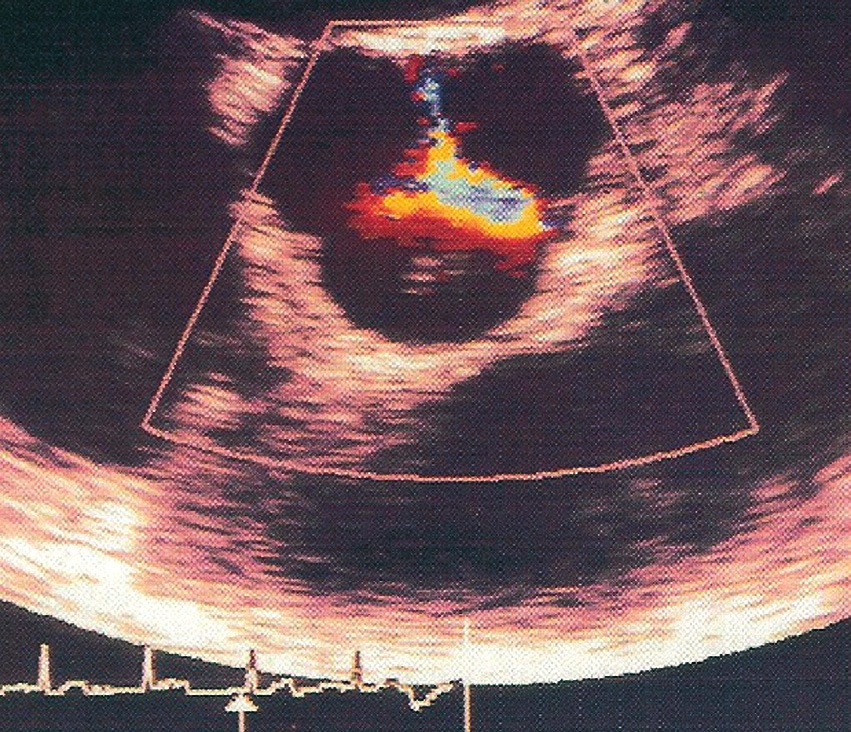

Respecto al primero de estos puntos, la ponderación de la insuficiencia requiere en primer lugar del análisis de la morfología valvular y luego, la integración de una serie de variables del doppler-color y espectrales, que cuantifican en forma precisa el grado de insuficiencia (Figuras 4 y 5). Entre ellos están:

Figura 5 Insuficiencia aortica bajo ecocardiografía transesofágica – Área de insuficiencia aórtica en una ecocardiografía transesofágica en eje corto.